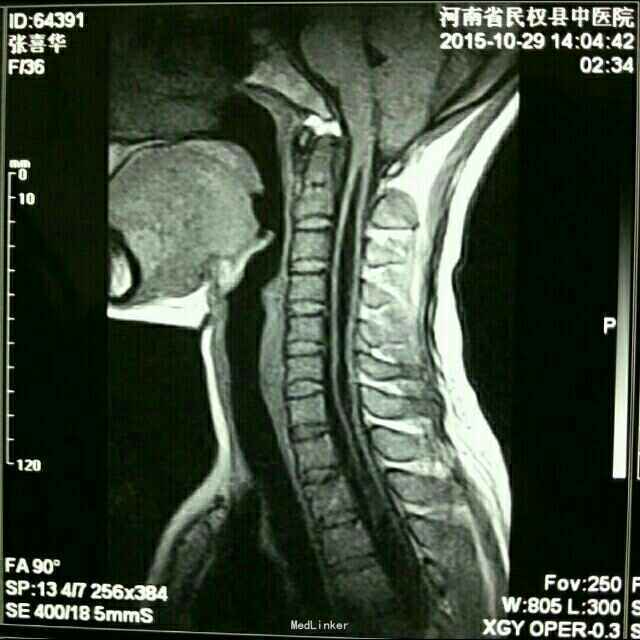

左上肢及胸背部麻木20年余。

左上肢及胸背部痛温觉减退,脊柱侧弯。

小脑扁桃体下疝并脊髓空洞症

链接【小脑扁桃体下疝畸形】 又名阿诺德-奇阿(Arnold–Chiari)畸形,为常见的先天性发育异常。是由于胚胎发育异常使小脑扁桃体下部下降至枕骨大孔以下、颈椎管内,严重者部分延髓下段、四脑室下部下蚓部也下疝入椎管内。常合并有脊髓空洞,也可引起脑脊液循环受阻引起脑积水。小脑扁桃体下疝畸形常伴其他颅颈区畸形如脊髓脊膜膨出颈椎裂和小脑发育不全等。可表现为头痛、头面部上肢力弱、肩臂部痛温觉减退、吞咽困 难、眩晕、恶心、共济失调、甚至瘫痪等症状。 【治疗方法】 小脑扁桃体下疝畸形的主要治疗手段为手术治疗,手术的目的是为了解除枕骨大孔和上颈椎对小脑、脑干脊髓、第四脑室及该区其他神经结构的压迫,在可能的范围内分离枕大池正中孔和上颈髓的蛛网膜粘连,解除神经症状,缓解脑积水。 目前民权县中医院脑外科已在高倍显微镜下成功开展该手术![微笑][微笑][微笑]